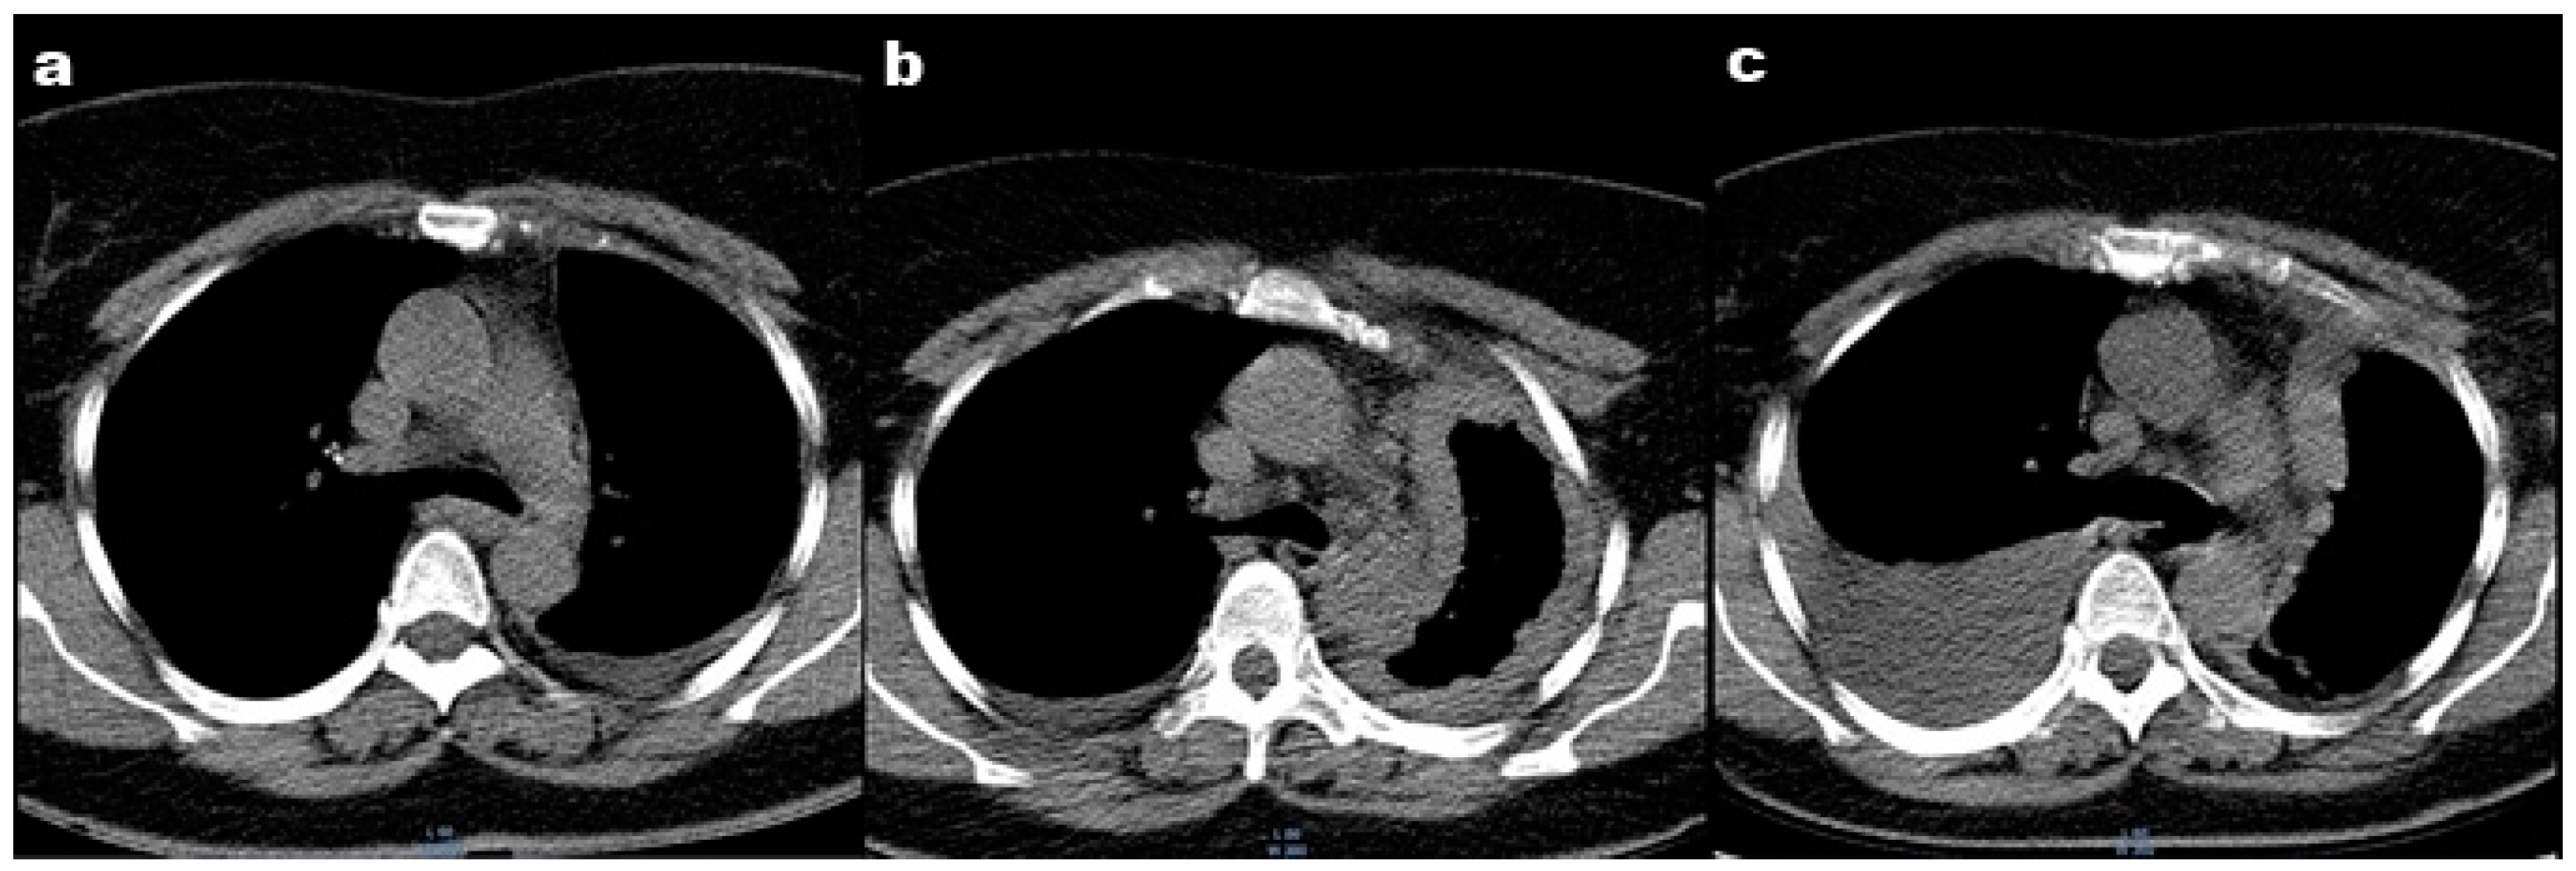

To assess the extension of the lesions, a positron emission tomography (PET-CT) was performed. The results showed the thickening of the left pleura from the top to the base. No metastases or invasion of the chest wall, mediastinum, or diaphragm were noted (Figure 2).

Regarding imaging investigations, chest X-rays are usually the first investigation to be performed, and it shows unilateral pleural effusion in 30–80% of cases. Computed tomography with contrast material is mandatory even for the initial evaluation and plays a leading role in staging, tracking the evolution, and establishing the therapeutic protocol [15]. PET-CT is a complementary investigation needed for differential diagnosis of benign pleural disorders as it can provide additional information on the metabolic function of tissues. Typically, in the case of mesothelioma, areas of abnormal pleural thickening show a higher consumption of the radiotracer as compared to benign pleural diseases [13].

Figure 2. PET-CT scans showing thickening of the left pleura from top to base. No metastases or invasion of the chest wall, mediastinum, or diaphragm.